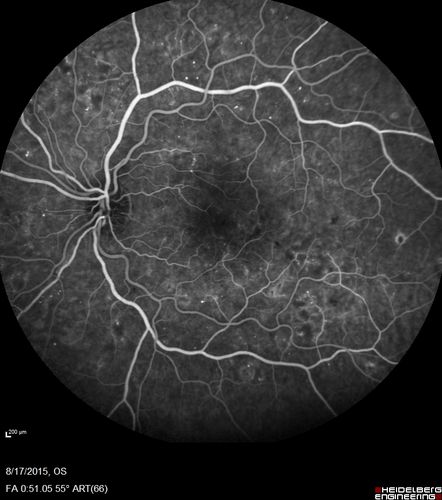

West Nile Virus Multifocal Choroiditis and diabetic retinopathy

Multifocal and clustered focal lesions are from west nile virus. The retinopathy is probably diabetic but could also be related to west nile virus